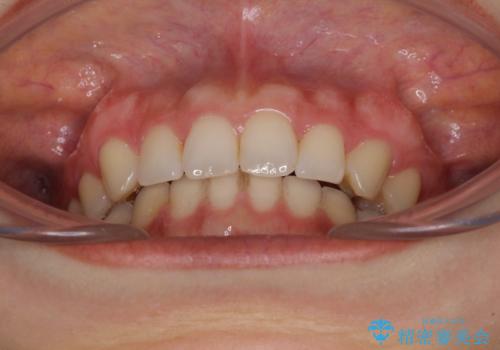

隙間だらけの歯列をきれいに インビザライン矯正とセラミック補綴治療

インビザラインにより下顎前歯の隙間を閉じるとともに、奥歯の咬み合わせを改善させることとしました。

矯正治療後には、銀歯のクラウンをセラミッククラウンへ替える補綴治療を行うこととしました。

1日22時間以上の装着時間をしっかりと守ってくださったので、順調に治療を進めることができました。